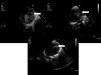

Paciente varón de 7 días de vida, al que se diagnostica de estenosis valvular aórtica severa, y se decide realización de valvuloplastia aórtica percutánea mediante abordaje retrógrado con catéter pig-tail por vía transaórtica. Se aprecia fractura de catéter dentro del ventrículo izquierdo, tras recambio del mismo se realizan inyecciones en ventrículo izquierdo, en las que se aprecia una imagen de fuga en pared antero-lateral del mismo limitada a la zona subepicárdica (fig. 1), correspondiente a pseudoaneurisma de boca muy estrecha. Se continua el procedimiento para disminuir la presión en ventrículo izquierdo, realizando la valvuloplastia percutánea (relación balón-anillo aórtico=0,9), con buen resultado. Se comenta con cirugía cardiaca y se decide mantener en observación, con controles ecocardiográficos frecuentes (Imagen 2). A los 2 días del procedimiento, presenta taponamiento cardiaco que requiere pericardiocentesis urgente y traslado del paciente a quirófano, donde se visualiza hemopericardio a tensión y hematoma intramiocárdico con zona disrupción amplia central, realizando sutura continua doble. No incidencias tras la cirugía. En los controles posteriores ha permanecido estable y libre de intervención.

El pseudoaneurisma del ventrículo izquierdo es frecuente como complicación mecánica del infarto agudo de miocardio en la edad adulta1. La etiología mas frecuente en la edad pediátrica es la traumática, bien accidental, o como consecuencia de procedimientos terapéuticos en cardiopatías congénitas2,3. Su tratamiento es quirúrgico, de forma urgente si existe compromiso hemodinámico, aunque hay ocasiones en que el propio tejido lo autoexcluye con cierre espontáneo, por lo que requiere en todo momento una vigilancia intensiva.